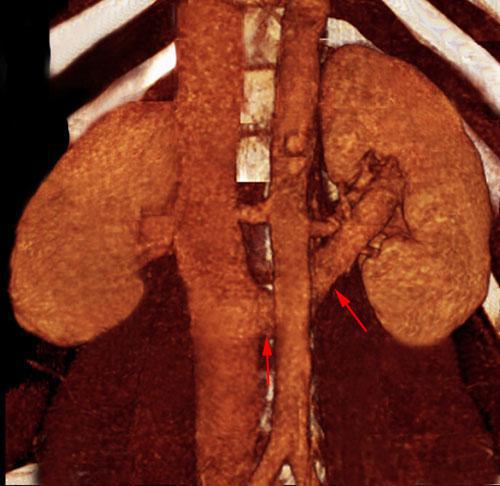

Síndrome del cascanueces retroaórtico